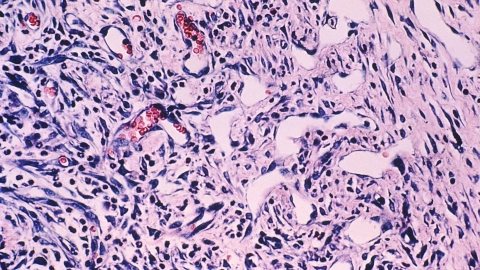

Sarkome sind seltene Tumoren. Es gibt davon über 100 verschiedene Unterformen. Sarkome treten vor allem im Weichgewebe, aber auch in den Knochen auf.

Mehr erfahren